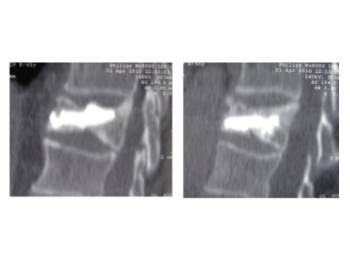

Comparació pre- i post-operatoria d’una cifopastia cementada

Dona, edat 55 anys, fractura aixafament dret de L2

Abans 1

Després 1

Abans 2

Després 2